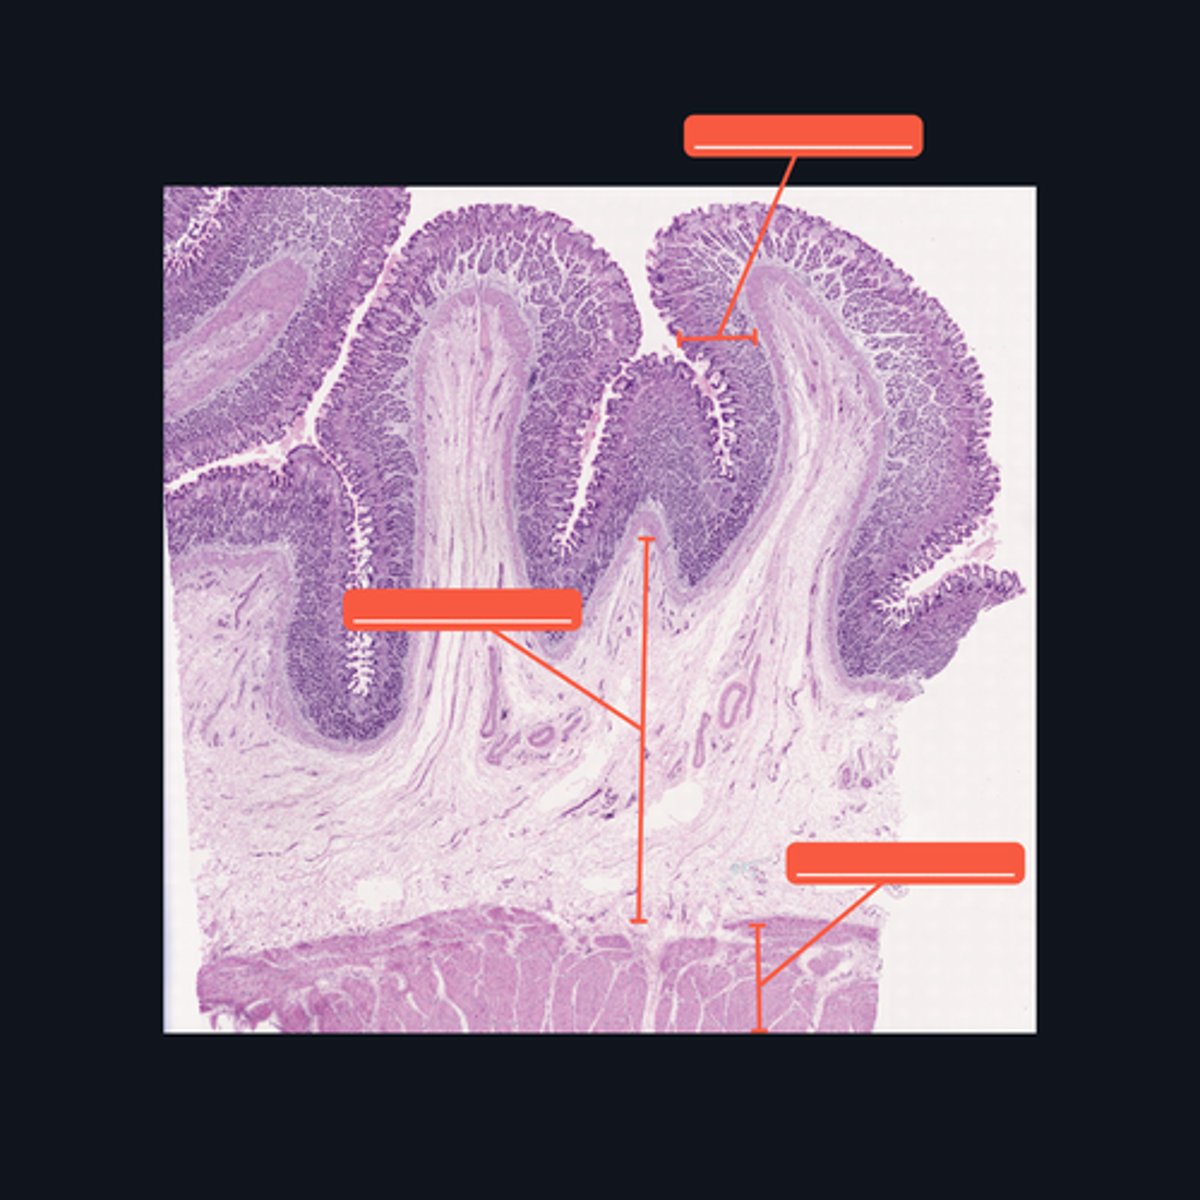

Mucosa, Submucosa, Muscularis Externa

Identify the histologic layers of the digestive tract

(1) Visceral Efferent Neuerons/ Autonomic Ganglion Cells

(2) Meissner's Plexus and Auerbach's Plexus

Cells from the division of the nervous system that innervates this specimen are made up of (1)_______, and whose cell bodies and fibers form (2) two ganglionated plexuses named: _______ and ________.

Submucosa

Identify the pointed histologic layer of the digestive tract

Muscularis Externa

Identify the pointed histologic layer of the digestive tract

Serosa

Identify the pointed histologic layer of the digestive tract